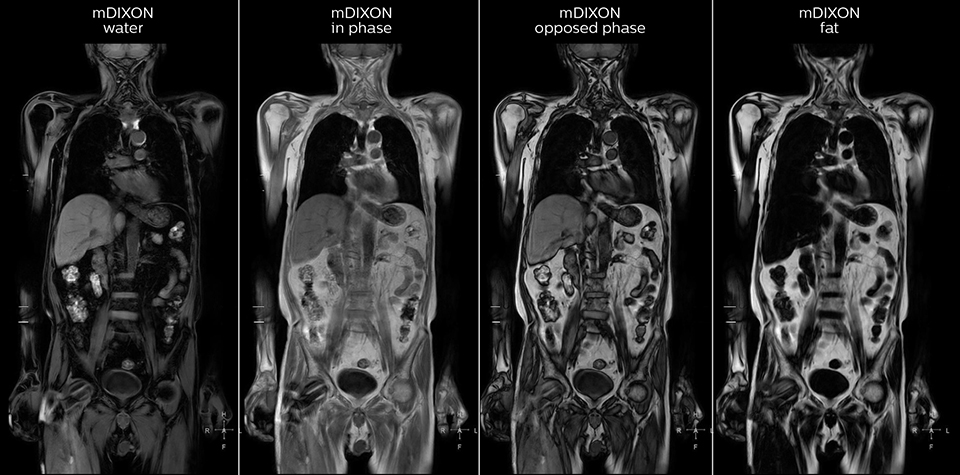

“mDIXON FFE allows us to quickly get information we need to assess the presence of fat. That gives us more information when we need to diagnose bone lesions, and when we are asked to judge fat-containing lesions such as hepatocellular or renal carcinoma,” Dr. Nobusawa says. “The mDIXON fat images can help us to differentiate fatty bone marrow from bone lesions. This is especially useful in elderly people, who tend to have fattier bone marrow. The water images provide a high signal-to-noise ratio in the intestinal canal, which is valuable for visualizing lesions in the colon,” he says.

Kawasaki Sawai Hospital’s whole body protocol also includes an mDIXON FFE sequence. Because mDIXON provides images for four contrast types – water only, fat only, in-phase and out-of-phase – from a single acquisition, it is useful in many ways.